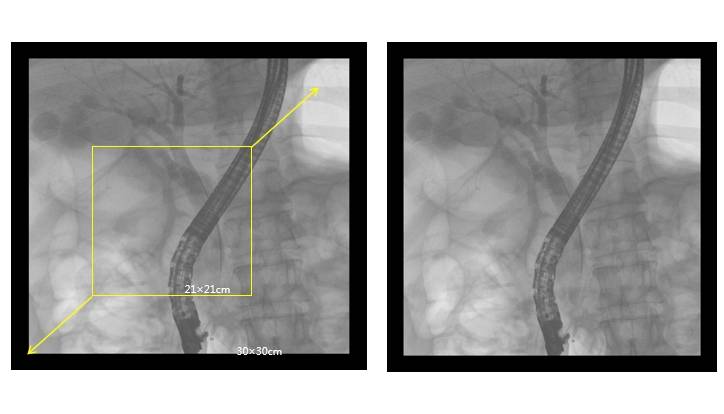

高端介入平板C形臂PLX7100A——ERCP臨床圖像:

介入平板C形臂PLX7100A圖像

廣闊視野:30cm×30cm的成像面積,能夠一次性全面覆蓋胸、腹、盆腔,減少了多次曝光和輻射的風(fēng)險(xiǎn),同時(shí)避免了檢查中的重疊和遺漏。

大尺寸平板探測(cè)器,成像面積提高一倍以上

普愛(ài)醫(yī)療高端介入平板C形臂PLX7100A,在多個(gè)方面展現(xiàn)出其優(yōu)越性。它不僅具備傳統(tǒng)胃腸機(jī)和小C臂無(wú)法比擬的性能,還特別增設(shè)了ERCP(內(nèi)鏡逆行性膽胰管造影)專(zhuān)用功能,滿(mǎn)足了復(fù)雜手術(shù)的需求。這款介入平板C形臂在設(shè)計(jì)上注重細(xì)節(jié)洞察,結(jié)合大尺寸數(shù)字平板探測(cè)器、寬廣的機(jī)械行程和診視空間,為臨床提供了低劑量、寬視野和高分辨率的影像,極大地增強(qiáng)了對(duì)ERCP等微創(chuàng)手術(shù)的支持能力。